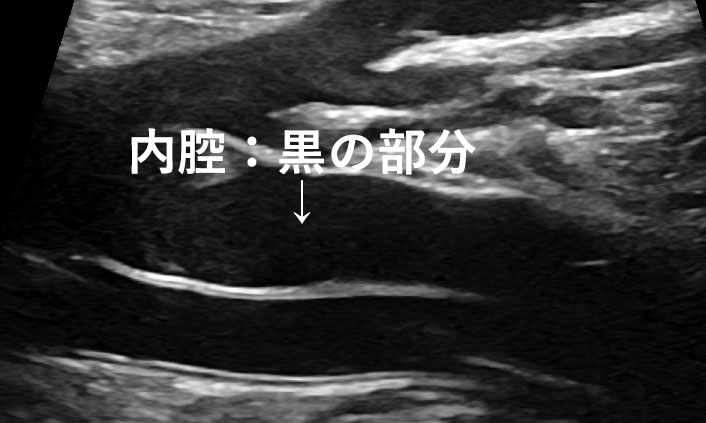

今まで、肝臓の脂肪化は「肝臓が腎臓より白い」「肝臓の深いところが黒い」「肝臓の血管などが見えづらい」といった見た目で評価をしていました。

肝脂肪化測定では、エコーの減衰を数値化できる最新技術で肝脂肪化の程度を計測します。

脂肪が肝臓へ推積すると超⾳波が通りにくくなる特徴(減衰)を利⽤して、肝脂肪化の程度を客観的な”数値“で把握できるようになりました。